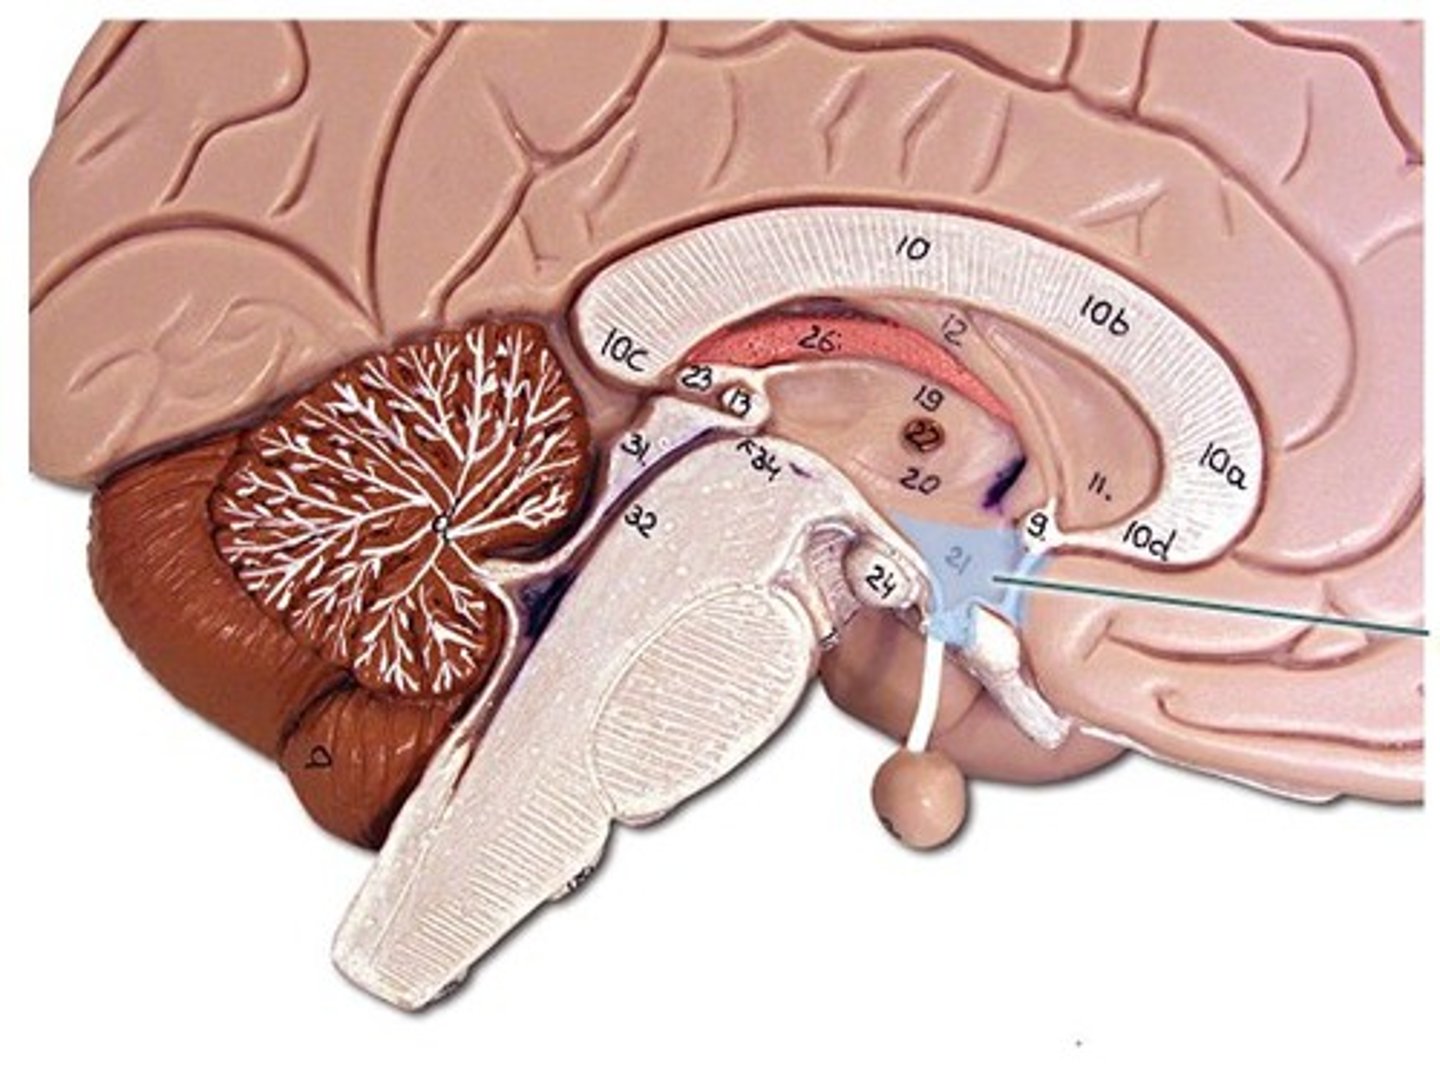

lateral ventricles

third ventricle

fourth ventricle

interventricular foramen

connects lateral ventricles to third ventricle

cerebral aqueduct

connects the third and fourth ventricles

choroid plexus

on the floor of all the ventricles, produces CSF

arachnoid villi

diencephalon

thalamus and hypothalamus

thalamus

relay station for all somatosensory information

intermediate mass

connection between the two thalami across the third ventricle, dumbbell shape

hypothalamus

brain region (many nuclei) in charge of maintaining homeostasis

pituitary gland

produces hormones

mammillary bodies

olfactory relay stations

epithalamus

region above midbrain that contains pineal gland

pineal gland

regulates sleep-wake cycles, secretes melatonin

cerebellum

balance, equilibrium, gross motor movement

corpus callosum

the large band of neural fibers connecting the two brain hemispheres and carrying messages between them

septum pellucidum

membrane that separates lateral ventricles

basal nuclei

internal masses of gray matter, smooth out motor movement

fornix

band under septum pellucidum